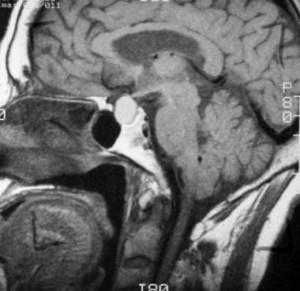

Т1-взвешенное сагиттальное изображение, полученное до контрастного усиления: видна хорошо определяемая киста в зоне турецкого седла, изоинтенсивная спинно-мозговой жидкости. Отмечается соответствующая норме высокая интенсивность сигнала задней доли гипофиза сзади.

![f5]()

На Т1-взвешенном корональном изображении она видна рамером чуть менее сантиметра в центральной части турецкого седла. Слегка гиперинтенсивна по сравнению со спинно-мозговой жидкостью.